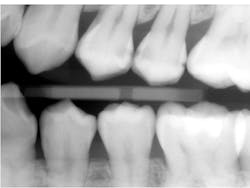

Below is the bitewing radiograph of my patient Lee (figure 4). Lee is a postgraduate student at a university near my office. He presented for a comprehensive examination, and we diagnosed a lot of decay in his dentition.

Many of the teeth that we diagnosed carious lesions on will eventually need indirect restorations, but our first goal is caries control. Two of his largest lesions happened to be on adjacent teeth, the distal of the upper left first premolar and the mesial of the upper left second premolar.